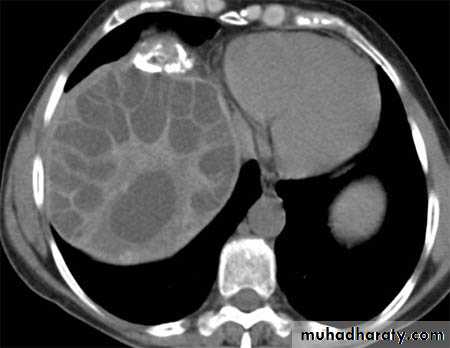

Hydatid cyst

Hydatid cystAppear as large oval hypo dense area density of fluid with well defined margin , sometime at their periphery multiple flecks of calcification are seen at their periphery .

Hydatid cyst with daughter cyst , appear as multiple hypo densities rounded area within the main loculi with multiple rim of

calcification

Hydatid cyst within the liver